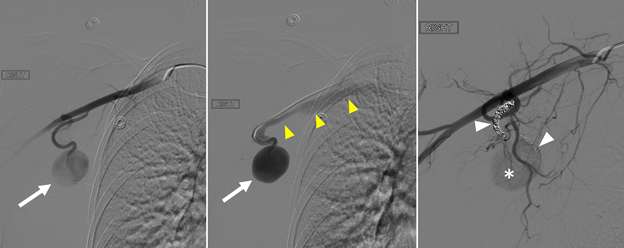

False aneurysm, or pseudoaneurysm, of the breast may be post-traumatic (blunt or penetrating), iatrogenic (e.g., post-biopsy, post-surgery), spontaneous (secondary to hemorrhage in the setting of coagulopathies or uncontrolled hypertension), or from vascular invasion by breast malignancy. The diagnosis of a breast pseudoaneurysm, if superficial, can often be made clinically by the presence of an expanding palpable, pulsatile mass on physcial exam. However, Doppler ultrasonography is the gold standard for confirming the diagnosis and characterizing the lesion for subsequent treatment planning (Figure 5). In the setting of acute trauma, breast and axillary pseudoaneurysms are usually identified radiographically during a trauma CT scan. Prompt treatment of pseudoaneurysms, especially if enlarging, is recommended in order to prevent clinically significant hemorrhage and rupture. The choice of therapy is guided by both clinical factors and imaging features, but generally involves an initial trial of manual external compression. This can be performed using an ultrasound probe, which allows the clinician to monitor treatment progress under real time visualization. More invasive intervention is warranted if there is persistent filling of the pseudoaneurysm sac, usually done in a step-wise fashion of increasing invasiveness. The first-line therapy is ultrasound-guided direct thrombin injection, which is only performed for pseudoaneurysms with features of a narrow (and preferably long) communication to the native artery origin (i.e., narrow "neck"). Thrombin injection is performed by slowly injecting a small volume of concentrated thrombin solution via direct needle puncture under constant ultrasound visualization. The procedure is well tolerated, however, there is a risk of distal embolization/migration which can lead to arterial thrombosis and ischemia; thus, thrombin injection should only be performed for pseudoaneurysms with a confidently seen narrow neck. Second-line therapies include endovascular treatment and surgical repair. Endovascular treatment is accomplished either via transarterial embolization of the sac using vascular coils and/or liquid embolic material, or by deploying a covered arterial stent across the pseudoaneurysm, thereby excluding the sac from arterial inflow. The latter is less preferable, as it requires post-treatment anticoagulation to mitigate the risk of in-stent thrombosis and stenosis. Surgical repair is generally reserved for refractory pseudoaneurysms or those with unfavorable anatomy. The operation is performed by surgically ligating across the pseudoaneurysm supply and resecting or evacuating the sac hematoma.